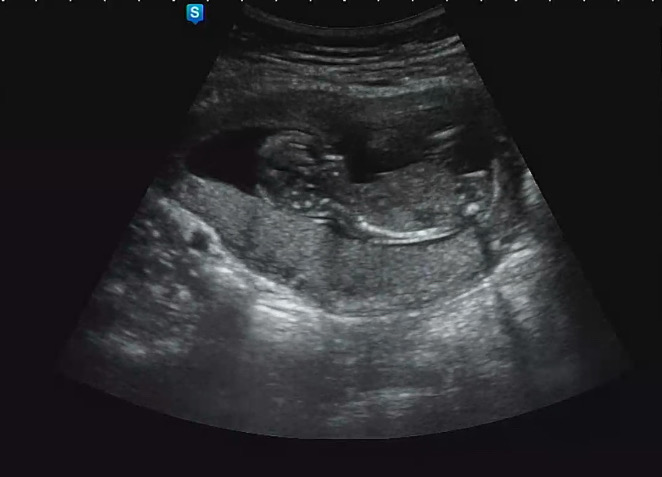

13주 3일 각도법 한번만 봐주세용!!!!

아들일까요? 딸일까요? 너무 궁금해서 올려봅니다! 각도법 한번반 봐주세용~~